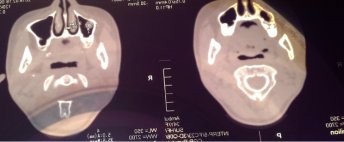

Во время планирования операции для импланта на томограмме обнаружилась киста на ранней стадии под гайморовой пазухой у семерки. Имплантолог говорит, что трогать необязательно, но на вопрос ― будет ли киста развиваться, отвечает утвердительно.

Выложите мне снимок, я отвечу Вам на остальные вопросы.